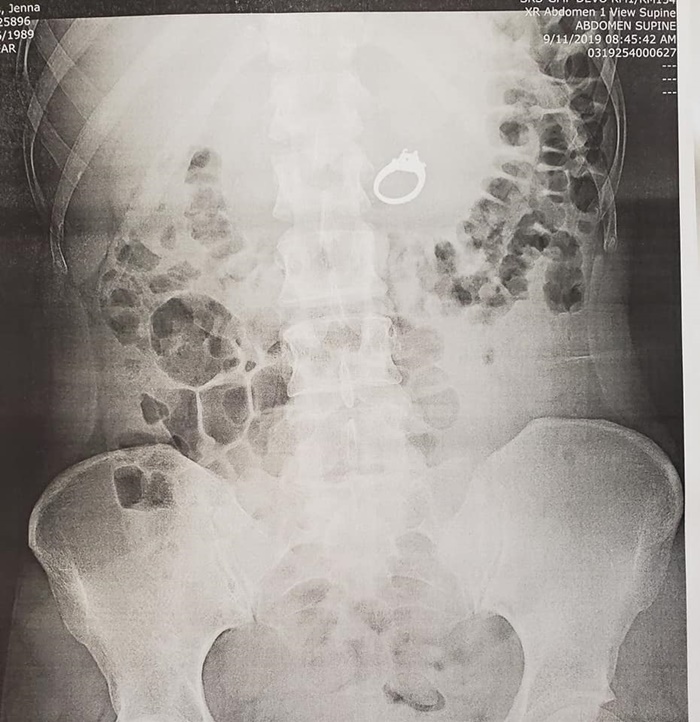

และแพทย์ก็ค่อนข้างช็อกเมื่อผลการเอกซเรย์เผยให้เห็นว่า

มีแหวนวงหนึ่งอยู่ภายในท้องของเจนนาจริง ๆ